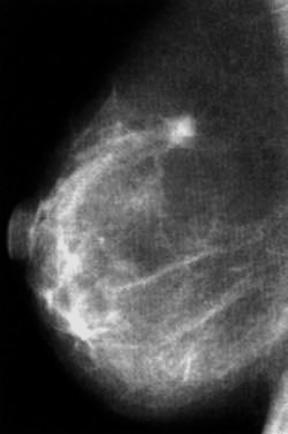

2.3.2.1.7 Mammografia

Si

vede nell¼immagine, sopra un po¼ a destra della mediana una calcificazione.